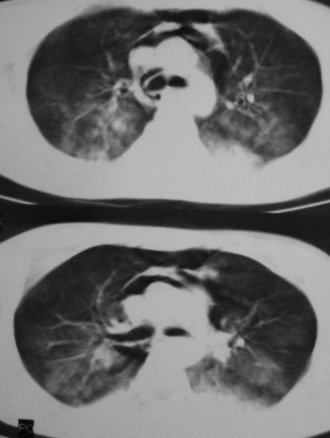

男,18岁,车祸20小时后胸ct.血氧饱和度80,呼吸45次/分.

1.双下肺挫伤;

2.纵隔积气。

两肺挫伤,纵隔气肿,两侧气胸